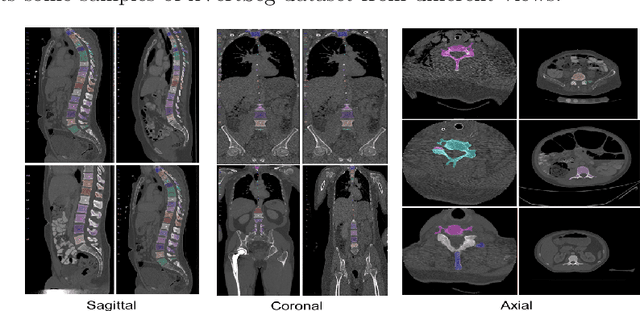

Accurate segmentation of the vertebra is an important prerequisite in various medical applications (E.g. tele surgery) to assist surgeons. Following the successful development of deep neural networks, recent studies have focused on the essential rule of vertebral segmentation. Prior works contain a large number of parameters, and their segmentation is restricted to only one view. Inspired by DoubleU-Net, we propose a novel model named DoubleU-Net++ in which DensNet as feature extractor, special attention module from Convolutional Block Attention on Module (CBAM) and, Pyramid Squeeze Attention (PSA) module are employed to improve extracted features. We evaluate our proposed model on three different views (sagittal, coronal, and axial) of VerSe2020 and xVertSeg datasets. Compared with state-of-the-art studies, our architecture is trained faster and achieves higher precision, recall, and F1-score as evaluation (imporoved by 4-6%) and the result of above 94% for sagittal view and above 94% for both coronal view and above 93% axial view were gained for VerSe2020 dataset, respectively. Also, for xVertSeg dataset, we achieved precision, recall,and F1-score of above 97% for sagittal view, above 93% for coronal view ,and above 96% for axial view.